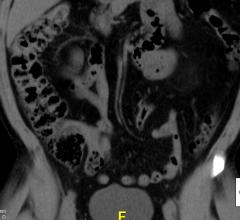

Feature | Sabah Servaes, M.D., and Sjirk J. Westra

Imaging children has challenges that relate to the size, maturity and anxiety of the patient. In addition, we have…

Feature | Dave Fornell

New computed tomography (CT) dose studies and growing public media attention have made minimizing unnecessary radiation…